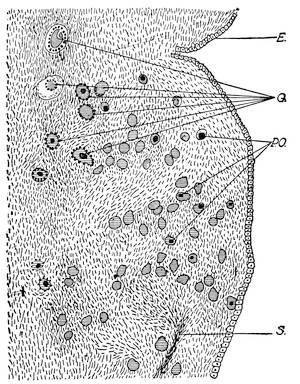

Mons of Venus, labia majora, minora, vestibule, bulbs, clitoris, Bartholinian glands, hymen, vagina, uterus, broad and round ligaments, viiitubes, ovaries, Graafian follicle, ovum.

Function of ovaries, ovum, Graafian follicle, tubes, menstruation, function of uterus, female ejaculation, function of vagina, Bartholinian glands, of clitoris, course of the sexual act.

Before the Wolffian body has yet degenerated the mesothelial cells overlying the free surface of that body, at its upper part, and at the ventro-mesial side, assume a high columnar form and form an elongated swelling, known as the internal genital ridge. As the degeneration of the Wolffian body proceeds the genital ridge is differentiated into the indifferent sexual gland, by producing a projection upon the wall of the coelom or body cavity. This prominence is attached to the surface of the Wolffian body by a fold of the peritoneum. At this stage there is no distinction of sex. The sexual gland represents the indifferent type of the sexual apparatus.

The ovary is produced from the asexual stage by the following metamorphosis. The mesothelial cells on the peritoneal surface of the sexual gland change into the germinal epithelium and form the so-called egg-columns or sexual cord which represent the primitive ova.